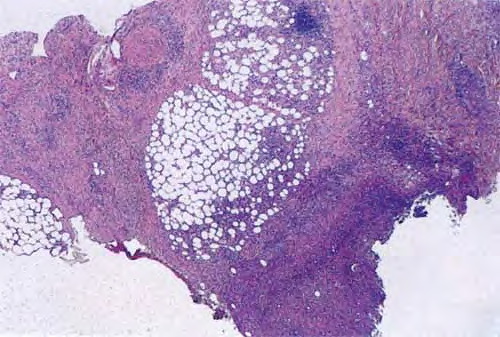

Erythema elevatum diutinum = الحمامى المرتفعة الدائمة Erythema Elevatum Diutinum This rare condition is characterized by persistent, initially red to violaceous and later brown to yellow papules, nodules, and plaques . The lesions, typically distributed symmetrically on the extensor surfaces of the extremities, are initially soft and then evolve into fibrous nodules. Histopathologic Features. In […]